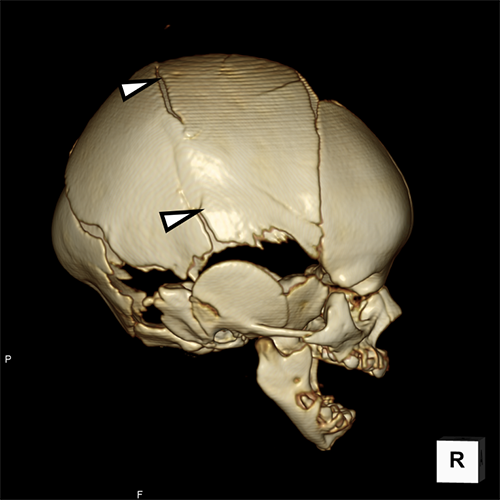

骨折の単純CT- 急性硬膜下血腫

- 頭蓋骨骨折

交通事故に遭ったり、転んだりして、頭や首などを受傷 (けが)した際に起こります。

軽いものであれば経過観察していきます。しかし、命に関わるような状態であったり、そのままにしておくと意識/高次機能や手足の動きに不自由が生じてしまう可能性がある場合は、緊急で手術を行います。北里大学病院では、主に救命救急・災害医療センターで全身管理を行い、救命救急・災害医療センター所属の脳神経外科医が手術を行っています。